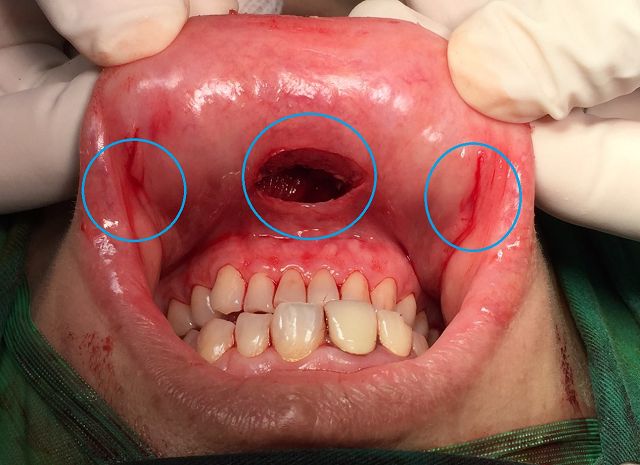

巫主任說,甲狀腺結節分為良性和惡性,且無痕微創手術也不同。良性結節可用第四代達文西機械手臂進行「自然孔洞達文西甲狀腺手術」,結合ICG螢光即時定位副甲狀腺,幫助仔細保留副甲狀腺及返喉神經,將甲狀腺結節病灶半側切除。惡性結節則須考慮腫瘤大小、侵犯程度與淋巴轉移範圍。國際普遍認為若腫瘤小於2公分,無甲狀腺外侵犯且有局部中央淋巴結轉移,可採用「自然孔洞達文西甲狀腺手術」;若大於2公分或有外側淋巴結轉移,採用「雙側經乳暈和腋下達文西甲狀腺手術」,避免頸部傷口疤痕,可由腳位至頭位的外側淋巴結清除,配合神經導引與ICG螢光保留副甲狀腺。若甲狀腺外侵犯鄰近器官,就不要勉強非用無痕手術,以根除性切除為主要考量。